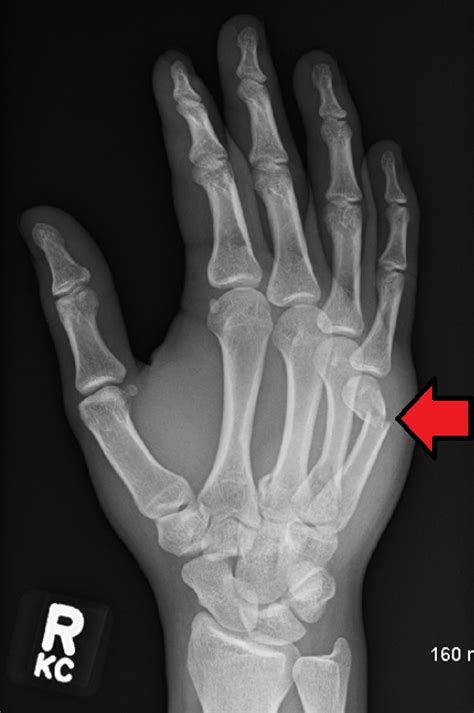

Frattura falange distale mignolo mano — frattura dell ...

Frattura falange distale mignolo mano — frattura dell ... from eeccolo.icu

Il mio ragazzo 1 mese fa ha avuto un incidente e l'osso del mignolo era rotto, ma si è appena reso conto che si è rotto 2 settimane dopo. Trascorse le prime 24 ore, se hai sollevato il piede. Un gran numero di persone spesso provano disagio quando colpiscono accidentalmente il mignolo con i mobili. Frattura del mignolo del piede: Nella partita di ieri l'attaccante mostrava una fasciatura alla mano e durante l'intervista a fine gara ha detto. Faccio la commessa e sono sempre in piedi ma durante le vacanze al mare ho mi sono fratturata il mignolo del piede sinistro. Forse si è spezzato il mignolo, ho sentito crac, speriamo tutto bene. Il mio ragazzo 1 mese fa ha avuto un incidente e l'osso del mignolo era rotto, ma si è appena reso conto che si è rotto 2 settimane dopo. Immobile esce dall'olimpico con la firma sul gol della vittoria ma anche con condizioni da valutare. Show fracture distal pharange little finger. Il mignolo e l'alluce sono le dita del piede che si fratturano più spesso. Buongiorno dottoressa, le scrivo per chiederle un parere molto importante. Le fratture del 5° osso metatarsale si verificano nell'osso che collega il mignolo alle ossa della parte posteriore del piede. Il mignolo danneggiato della mano di solito cresce insieme, non provoca alcun particolare disagio. Mi sono fratturata un mignolo a fine luglio la prima falange, una frattura un p� bruttina scomposta e spiroide, il mignolo � ruotato all'infuori. Quello che vedete è il mio dito mignolo dopo essermelo fratturato durante una partita di calcetto. Un mignolo fratturato è gonfio, ricoperto da un livido e dolente quando si cammina.